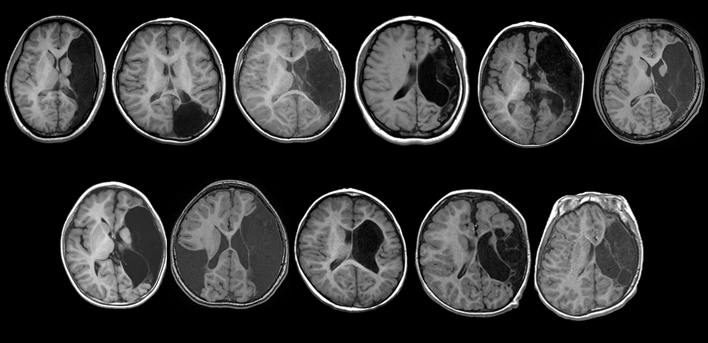

図2

• 対象は、孔脳症に伴う難治てんかん発作を有し、てんかん外科治療をおこなった11例。

• 孔脳症は全例で左側にみられた(うち1例では両側性)

• 10例では中大脳動脈領域、1例では後大脳動脈領域に孔脳症を認めた。

• 11例中の10例で術前から右片麻痺を認めた。